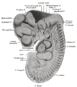

الدراسة البيولوجية للدماغ البشري يشكل أساس هذا الحقل المتداخل الذي يتضمن العديد من مستويات الدراسة , من المستوى الجزيئي إلى المستوى الخلوي (العصبونات المفردة) , إلى مستوى التجمعات الصغيرة نسبيا من العصبونات مثل cortical columns , و الجمل الفرعية الأكثر تعقيدا مثل ساحات الإدراك البصري visual perception , و حتى الجمل العصبية الضخمة مثل القشرة المخية cerebral cortex و المخيخ cerebral cortex كأعلى مستويات التعقيد ضمن الجهاز العصبي .